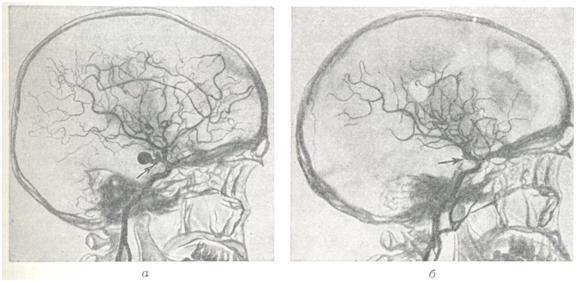

Диагноз.Появление перечисленных выше симптомов в молодом возрасте (чаще на 2—3-м десятилетии жизни) дает основание для предположения артерио-венозной аневризмы. Диагноз может быть поставлен лишь на основании всестороннего ангиографического исследования. Для выявления приводящих артерий и рано заполняющихся дренирующих вен необходима серийная ангиография с наибольшим числом снимков в первые 2—3 секунд. Лечение.Консервативное лечение является по существу симптоматическим и заключается в применении противосудорожных препаратов: фенобарбитал, дилантин и другие. При кровоизлияниях необходимо проведение коагулянтной и гипотензивной терапии. Лучевая терапия при артерио-венозных аневризмах неэффективна. Радикальным методом лечения является полное иссечение артерио-венозной аневризмы (рис. 4). Однако при большой распространенности аневризм и их расположении в глубинных, жизненно важных структурах мозга такая операция может оказаться невыполнимой. В подобных случаях могут применяться операции, уменьшающие приток крови к аневризме или приводящие к частичному выключению аневризмы,— окклюзия приводящих артерий, эмболизация артерио-венозной аневризмы и некоторые другие. Показания к той или иной операции должны быть строго индивидуальными; они определяются особенностями клинического течения, в частности количеством и тяжестью перенесенных кровоизлияний, локализацией, распространенностью аневризмы, характером ее кровоснабжения и опытом хирурга. В связи с совершенствованием техники операций, в частности широким использованием микроваскулярпой техники, показания к радикальному удалению артерио-венозных аневризм ставятся более широко, в том числе и при аневризмах, располагающихся в функционально важных зонах (речевой, двигательной). При радикальном удалении крупных, богато васкуляризируемых аневризм операцию следует начинать с выключения приводящих артерий. Благодаря этому уменьшается кровенаполнение аневризмы, а следовательно, меньше кровопотеря. При небольших поверхностно расположенных артерио-венозных аневризмах допустимо первоначальное выключение дренирующей вены; аневризма при этом наполняется кровью и более четко контурируется. Удаление аневризм, особенно расположенных в функционально важных областях, следует производить, выделяя сосудистый клубок по границе с мозгом, оставляя на поверхности аневризмы лишь тонкий слой измененного мозгового вещества. Важно при этом все время манипулировать вне пределов сосудистого клубка аневризмы, поскольку повреждение целостности ее сосудов приводит к сильному кровотечению, которое трудно остановить. Наличие внутримозговых гематом облегчает обнаружение аневризмы. Иногда гематомы как бы отслаивают часть аневризмы от мозга и тем самым упрощают ее удаление. При небольших глубоко расположенных аневризмах для облегчения их обнаружения во время операции могут быть использованы принципы стереотаксической нейрохирургии. Предварительно на основании расчетов по ангиограммам в область расположения аневризмы вводится направитель, по которому затем осуществляется подход к ней. При невозможности радикального удаления аневризмы может быть применено выключение приводящих артерий. Хотя этим путем обычно не удается достигнуть излечения и спустя некоторое время развиваются новые источники кровоснабжения артерио-венозной аневризмы, такая операция может привести к ослаблению кровотока в ней и уменьшить возможность повторных кровоизлияний. При больших, богато васкуляризированных аневризмах может быть осуществлена эмболизация сосудов аневризмы с помощью рентгеноконтрастных эмболов. С этой целью обычно используются различного размера пластиковые шарики, которые вводят через обнаженную на шее сонную (иногда вертебральную) артерию. В связи с резким ускорением тока крови в аневризме эмболы устремляются в ее сосуды. Таким образом иногда удается выключить из кровообращения значительную часть артерио-венозной аневризмы (рис. 5). Выполнение подобной операции требует точных представлений о характере кровоснабжения аневризмы, о диаметре, месте отхождения приводящих артерий и прочего. Каждый этап операции нужно контролировать повторным ангиографическим исследованием. Несоблюдение этих предосторожностей может привести к попаданию эмболов в нормальные сосуды мозга. Для направленного выключения сосудов, кровоснабжающих аневризму, а также для лечения других сосудистых поражений мозга (каротидпокавернозные соустья, некрые формы артериальных аневризм) применяют так называемые ангиотаксические операции. Смысл этих операций заключается в том, что подход к пораженному участку осуществляется по кровеносному руслу внутри просвета сосуда. С этой целью используют специальные катетеры, снабженные окклюзирующим баллончиком (Ф. А. Сербиненко, 1971). Такой катетер может быть направленно введен в приводящий сосуд артерио-венозной аневризмы посредством пункции сонной артерии на шее. Конструкция катетера позволяет произвести окклюзию сосуда, оставив в артерии баллончик, заполненный быстротвердеющим пластическим веществом, а катетер извлечь (рис. 6). Делаются попытки хирургического лечения артерио-венозных аневризм путем их замораживания с помощью жидкого азота. При аневризмах большой вены мозга, вызывающих окклюзию путей цереброспинальной жидкости, если нет условий для их удаления, возникают показания для разгрузочной операции с отведением цереброспинальной жидкости из желудочков мозга в венозное русло (вентрикуло-аурикулостомия). При тотальном удалении артерио-венозной аневризмы полностью исчезает опасность повторных кровоизлияний, прекращаются или становятся реже эпилептические припадки. Наступает нормализация кровообращения в головном мозге: при контрольном ангиографическом исследовании отмечается нормализация просвета ранее расширенных артерий, не заполняются дренирующие вены, лучше контрастируются сосуды областей мозга, прилегавших к аневризме. Летальность при тотальном удалении артерио-венозных аневризм колеблется в широких пределах и определяется прежде всего показаниями для хирургического лечения. По литературным данным, средняя послеоперационная летальность составляет приблизительно 10%, но при правильном определении показаний и использовании современных хирургических возможностей могут быть достигнуты лучшие результаты.